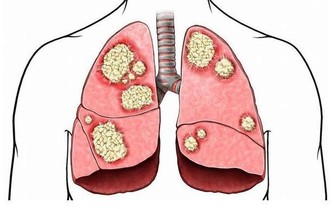

常見可能造成骨質疏鬆的藥物

1、增加維生素D的代謝:Phenytoin(癲癇治療)、Phenobarbital(癲癇治療)。

2、增加骨代謝:Valproicacid(精神科用藥)、Cyclosporin(控制器官移植後排斥作用)、Heparin(血栓性栓塞症及其預防)。

3、減少骨生成:Ifosfamide(抗癌藥)、Prednisolone(緩解發炎及過敏癥狀)。

4、減少血清鈣的濃度:Carbamazepine(癲癇治療、三叉神經痛)。